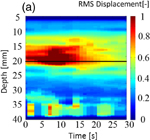

Figure 8 shows (a) an M-mode image of LMI displacement map and (b) an image of a normalized LMI displacement map. The horizontal and vertical axes are the time axis and the distance from the surface of the target sample in the depth direction, respectively. The focal point in the propagation direction is located at a depth of 17 mm [indicated by the solid line in Figs. 8(a) and 8(b)]. In an M-mode image, the tissue deformation occurred near the focal region and the magnitude decreased over time. To detect the beginning of coagulation and the formation of a coagulated region, measured displacement was normalized by the initial displacement at each depth. Figure 8 indicates a decreased ratio, and the coagulation size was estimated from the decreased region using a threshold of 0.8 (i.e., less than 80% of the initial displacement). Growth of the coagulated area is observed in this image.

Standard image High-resolution imageFig. 8. (a) M-mode image of LMI displacement map and (b) image of a normalized LMI displacement map (L = 20 mm, 20 °C, 30 s ablation).